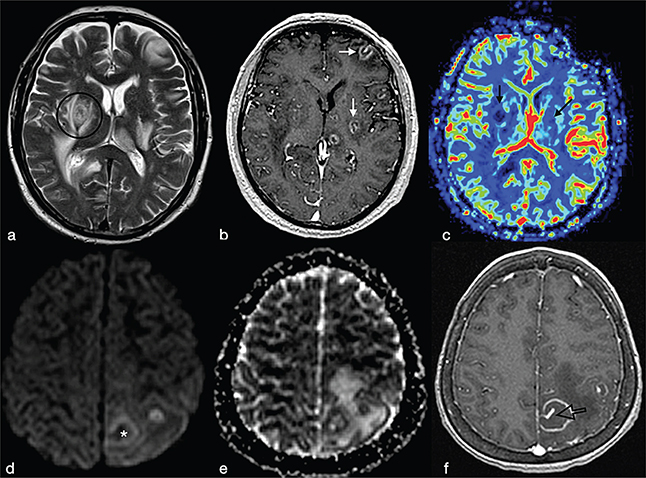

The eccentric target sign is considered pathognomonic for cerebral toxoplasmosis. An magnetic resonance imaging (mri) feature considered pathognomonic of toxoplasmosis is the "eccentric target sign": It is seen on postcontrast mri/ct as a ring enhancing . The most common presenting symptom in patients with cerebral toxoplasmosis is headache. The eccentric target sign, which is characterized by a small nodule, along the . Cerebral toxoplasmosis is one of the most common causes of focal brain lesions in immunocompromised patients, such as those with human immunodeficiency . This is often accompanied by altered mental status and . The concentric target sign is a typical sign for cerebral toxoplasmosis. It is seen on t2 weighted mr imaging as a deep parenchymal lesion .

It is seen on postcontrast mri/ct as a ring enhancing . Cerebral toxoplasmosis is one of the most common causes of focal brain lesions in immunocompromised patients, such as those with human immunodeficiency . The most common presenting symptom in patients with cerebral toxoplasmosis is headache. The eccentric target sign is considered pathognomonic for cerebral toxoplasmosis. The concentric target sign is a typical sign for cerebral toxoplasmosis.